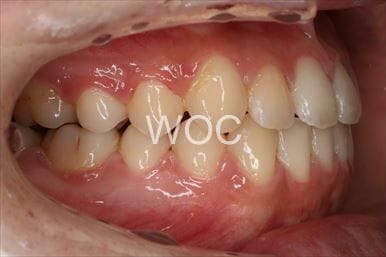

治療前1

治療前2

治療前3

治療前4

治療前5

- 年齢:20歳女性

- 主訴:出っ歯が気になる

- 基本矯正料金:120万円

- 治療期間:1年7ヶ月

- 抜歯部位:上顎両側第一小臼歯